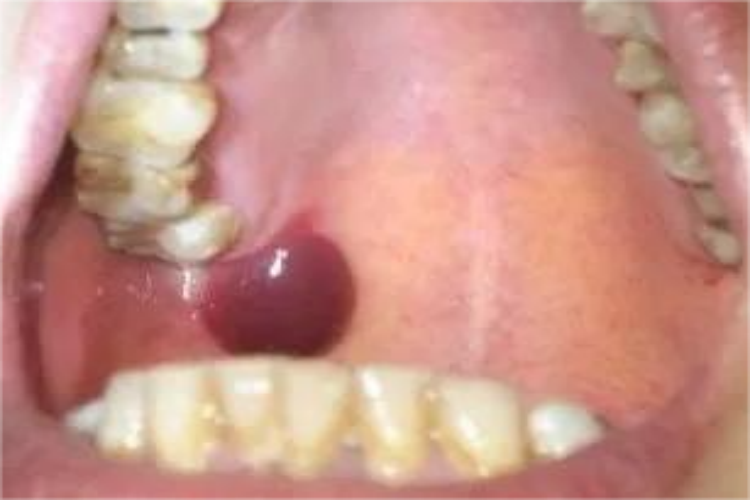

口腔上颚肿了一个包,考虑可能是外伤或口腔纤维瘤,其临床表现有所差异。

口腔纤维瘤:发生在口腔的纤维瘤较小,呈结节状,有蒂或无蒂,多发生于腭、颊等部位。质地坚硬,大小不等,表面光滑、边界清楚。继发感染时可引起疼痛或者功能障碍。